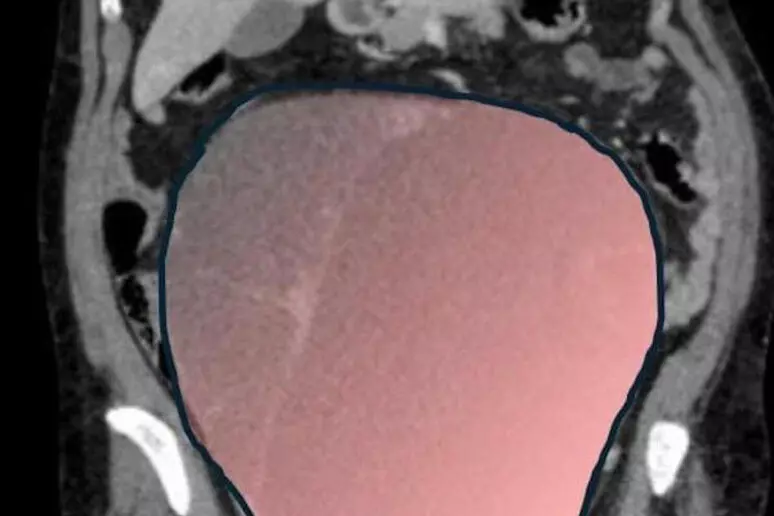

Un tumore ovarico di sei chilogrammi, con un diametro di 28 centimetri e un volume paragonabile a quello di una gravidanza gemellare a termine. È quanto è stato rimosso con un intervento chirurgico d’urgenza durato circa sei ore a Torino, salvando la vita a una donna di 69 anni.

La paziente, Daniela, è entrata in sala operatoria la mattina del 23 dicembre, dopo un improvviso peggioramento delle condizioni cliniche. Fino a pochi giorni prima, infatti, non aveva avvertito alcun dolore. La presenza di una seconda neoplasia intestinale ha però causato la compressione del colon, provocando sintomi acuti e una grave sofferenza intestinale che hanno reso necessario un intervento immediato.